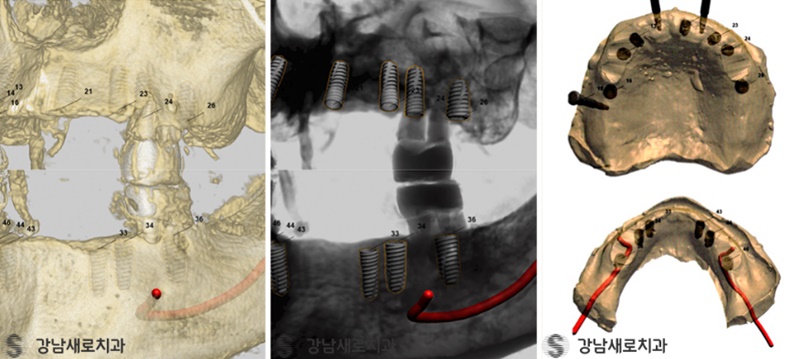

컴퓨터로 위치와 방향을 설정하는 모습

식립 전 컴퓨터 시뮬레이션을 통해

가상으로 모의 수술을 선행함으로써

최적화된 식립 경로(위치, 방향)를 사전에

설정할 수 있는 수술 방식입니다.